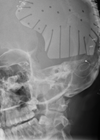

The role of objective measures and imaging to optimise cochlear implant outcomes

Should we be using new or novel objective measures and imaging to assist with our cochlear implant patients? Debi Vickers and Shak Saeed describe current clinical techniques and present advances that have the potential to optimise outcomes. Introduction It is...